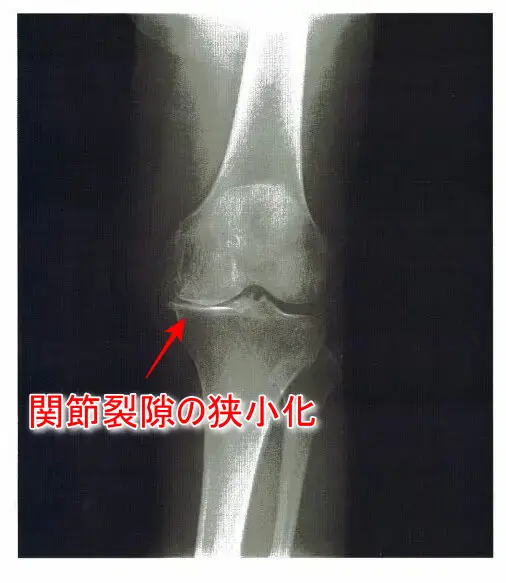

9 73歳の女性。3年前から特に誘因なく歩行時の左膝痛が出現し、徐々に悪化してきたため外来を受診した。左膝の熱感、腫脹なく関節裂隙の圧痛を軽度に認めた。立位のX線写真を下に示す。

・立位のX線写真:膝関節内側の関節裂隙の狭小化あり。